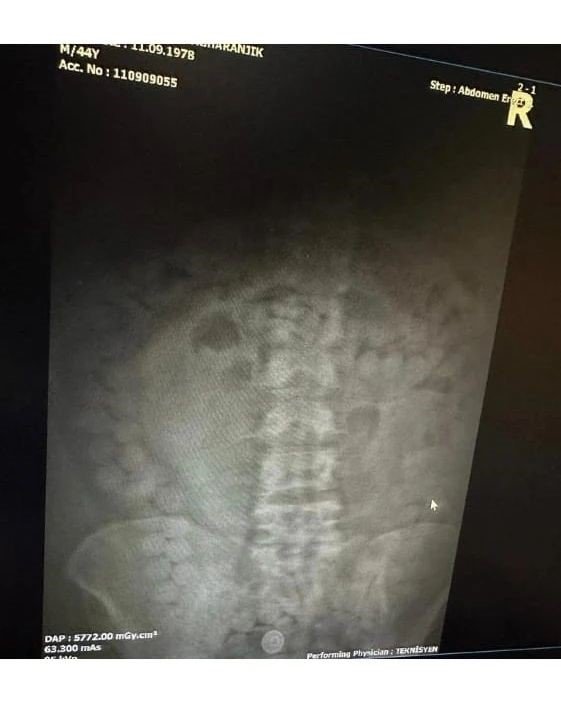

Narkotik Suçlarla Mücadele Şube Müdürlüğü ile Kaçakçılık ve Organize Suçlarla Mücadele Şube Müdürlüğü ekiplerince yapılan yol uygulamalarında İran uyruklu M.Z. (45) isimli şahıstan şüphelenilmesi sonucu iç beden muayenesi kararına istinaden yapılan tomografi çekiminde mide ve bağırsak kısmında uyuşturucu olabileceği değerlendirilen çokça yabancı cismin olduğu görüldü.

Yapılan tetkikler neticesinde M.Z. isimli şahıstan 101 adet kapsül halinde 848,82 gram Afyon sakızı ele geçirildi.